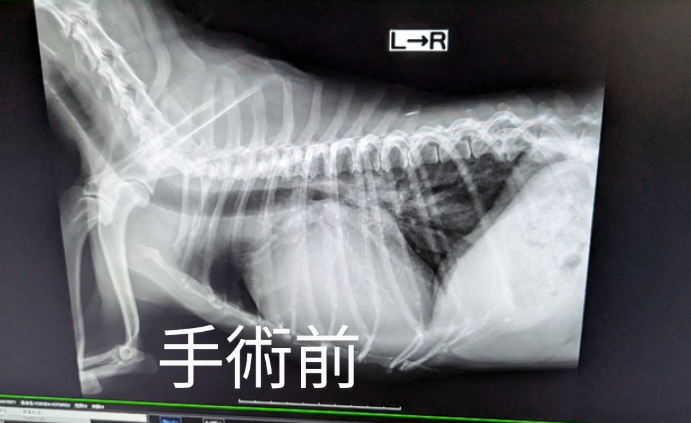

月日が経つのは早いもので半年検診となりました。虎太郎は退院後も何かしらの懸念点があった為に小刻みな検査でしたが2ヶ月空くと久々な感じがありますね🙃

結果でいうと良い所と悪い所がありまして、良くなったのは心臓のサイズが縮んでおりました。4ヶ月検診の頃はこれ以上縮むのはないかなぁという温度感だったのですが、3ヶ月前と比べて結構縮んでおりました✨